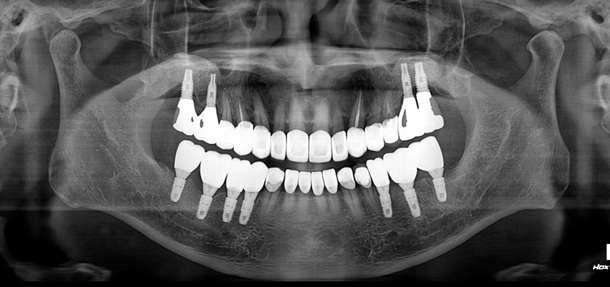

After

양측 어금니를 모두 임플란트 보철로 마무리 한 증례입니다.

이런 케이스에서 보철 완료 후 시간이 조금 지났을 때 어금니가 잘 닿지 않게 되는 경우가 종종 있습니다.

분명히 닿게 해 놨는데도 임플란트 보철 후 저작활동이 활발해 지면서 턱의 위치가 재정립 되고

위치가 변하면서 뒤쪽이 뜨게 되는 것이죠.

임플란트 보철은 시간적인 요소도 같이 고려하며 추적 관찰 해야 합니다.